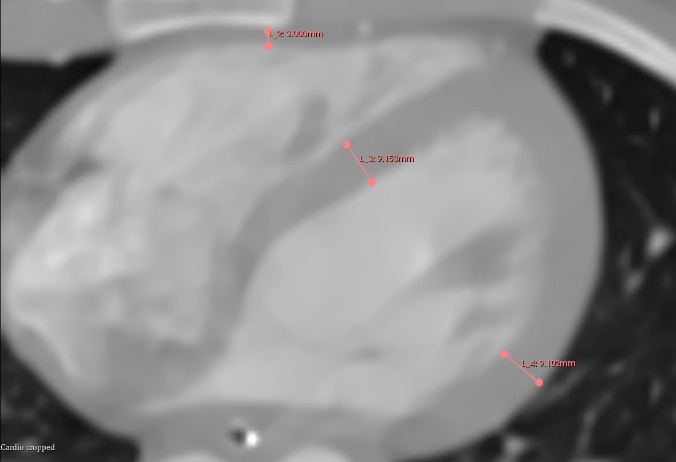

Figure 1 shows that the RV anterior wall measures approximately 3 mm, while the LV walls are about three times thicker. This discrepancy evidently contributes to the significant difference in force generation and the ability to withstand elevated afterload.

Figure 1. Computer tomography scan of a normal heart